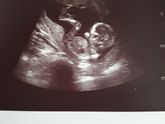

Узи с мужем!

Сходили на Узи сегодня, все хорошо соответсвует сроку?наконец-то лялю увидели? Мальчик будет у нас?на узи карапуз спал, я думала "факи" нам будет показывать, но сын решил по другому?